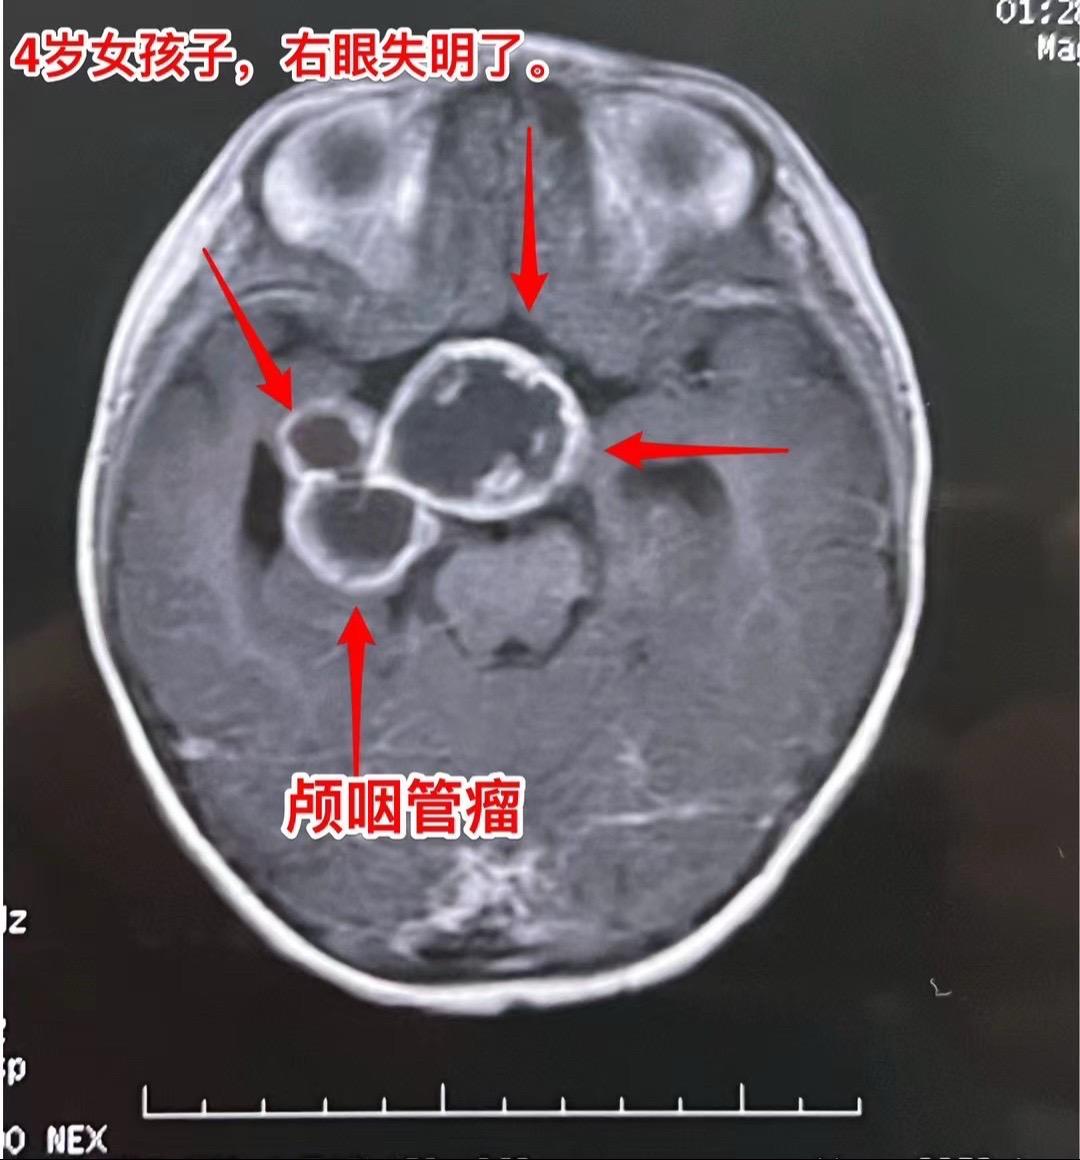

四岁怀化市女孩不幸遭遇了慢性硬膜下血肿。四岁女孩子因为右眼失明了,于今年的三月七日在我科作了颅咽管瘤切除手术。前六张照片是当时的照片,可以看见肿瘤体积大,幸运的是当时肿瘤得到完全切除,手术后小孩子也顺利出院。 12月15日小孩子身体状态很好,按时去复查磁共振,却发现脑部出现了硬膜下血肿,如图7-9所示,左侧的硬膜下血肿体积很大,压迫脑实质,所以,应该作手术了。 患儿和家长于12月16日一早赶到北京来办理住院手续。今天就作了手术,手术后作CT检查,显示血肿引出后左侧脑实质受压